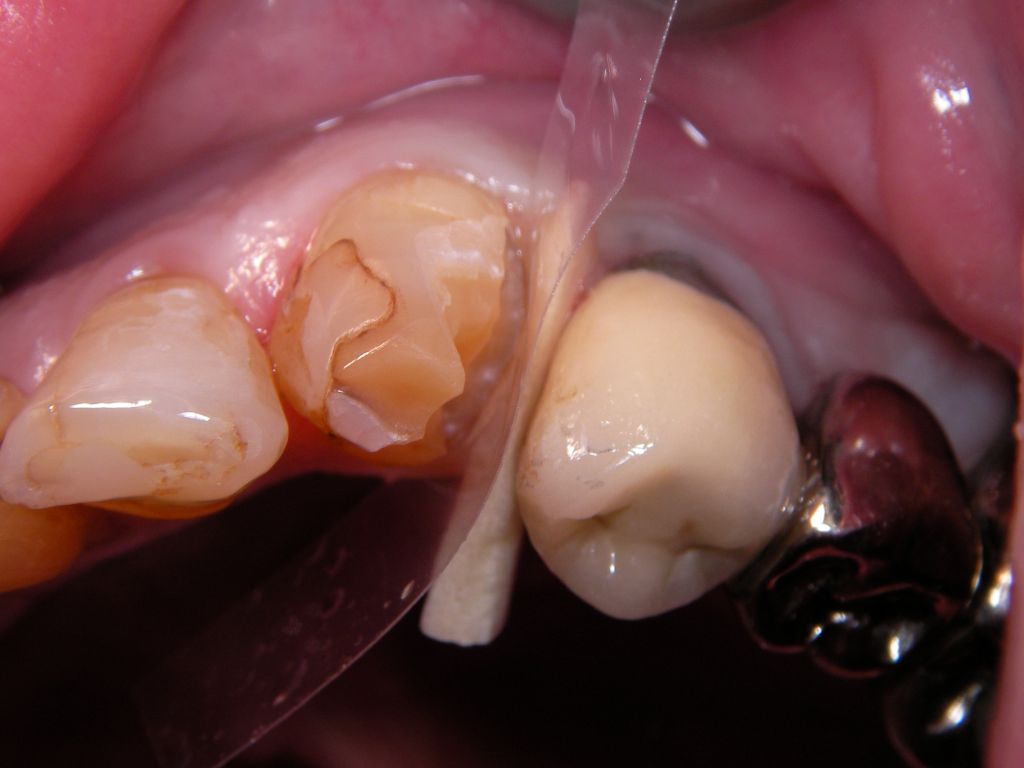

![]() | Von den 3 Kompositfüllungen des Zahnes sollen die beiden zu den Nachbarzähnen hin, rechts und links ("mesial" und "distal"), ersetzt werden. Ich habe das nacheinander gemacht, weil die Füllungen jeweils sehr groß waren und sonst die Situation schwieriger zu kontrollieren gewesen wäre. |

Links das Ergebnis am rechten Eckzahn im Unterkiefer nach Ersatz beider Füllungen. Am benachbarten Zahn 42 wurde die Rand- und Füllungsverfärbung einfach durch Politur entfernt - eine Erneuerung der Füllung war nicht notwendig. Eine Zuzahlung für den Kassenpatienten ist hier nicht angefallen. Alle Defekte des Eckzahnes zusammengenommen sind so groß, daß man sicherlich auch eine Krone hätte vertreten können. | |||||||||||||||||||||||||||||||||||||||||||||||||||||||||||||||||||||||||